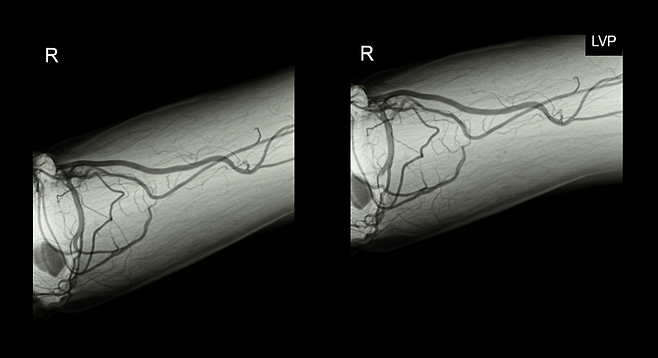

- 영상검사(CT, 혈관조영술, 혈관초음파)